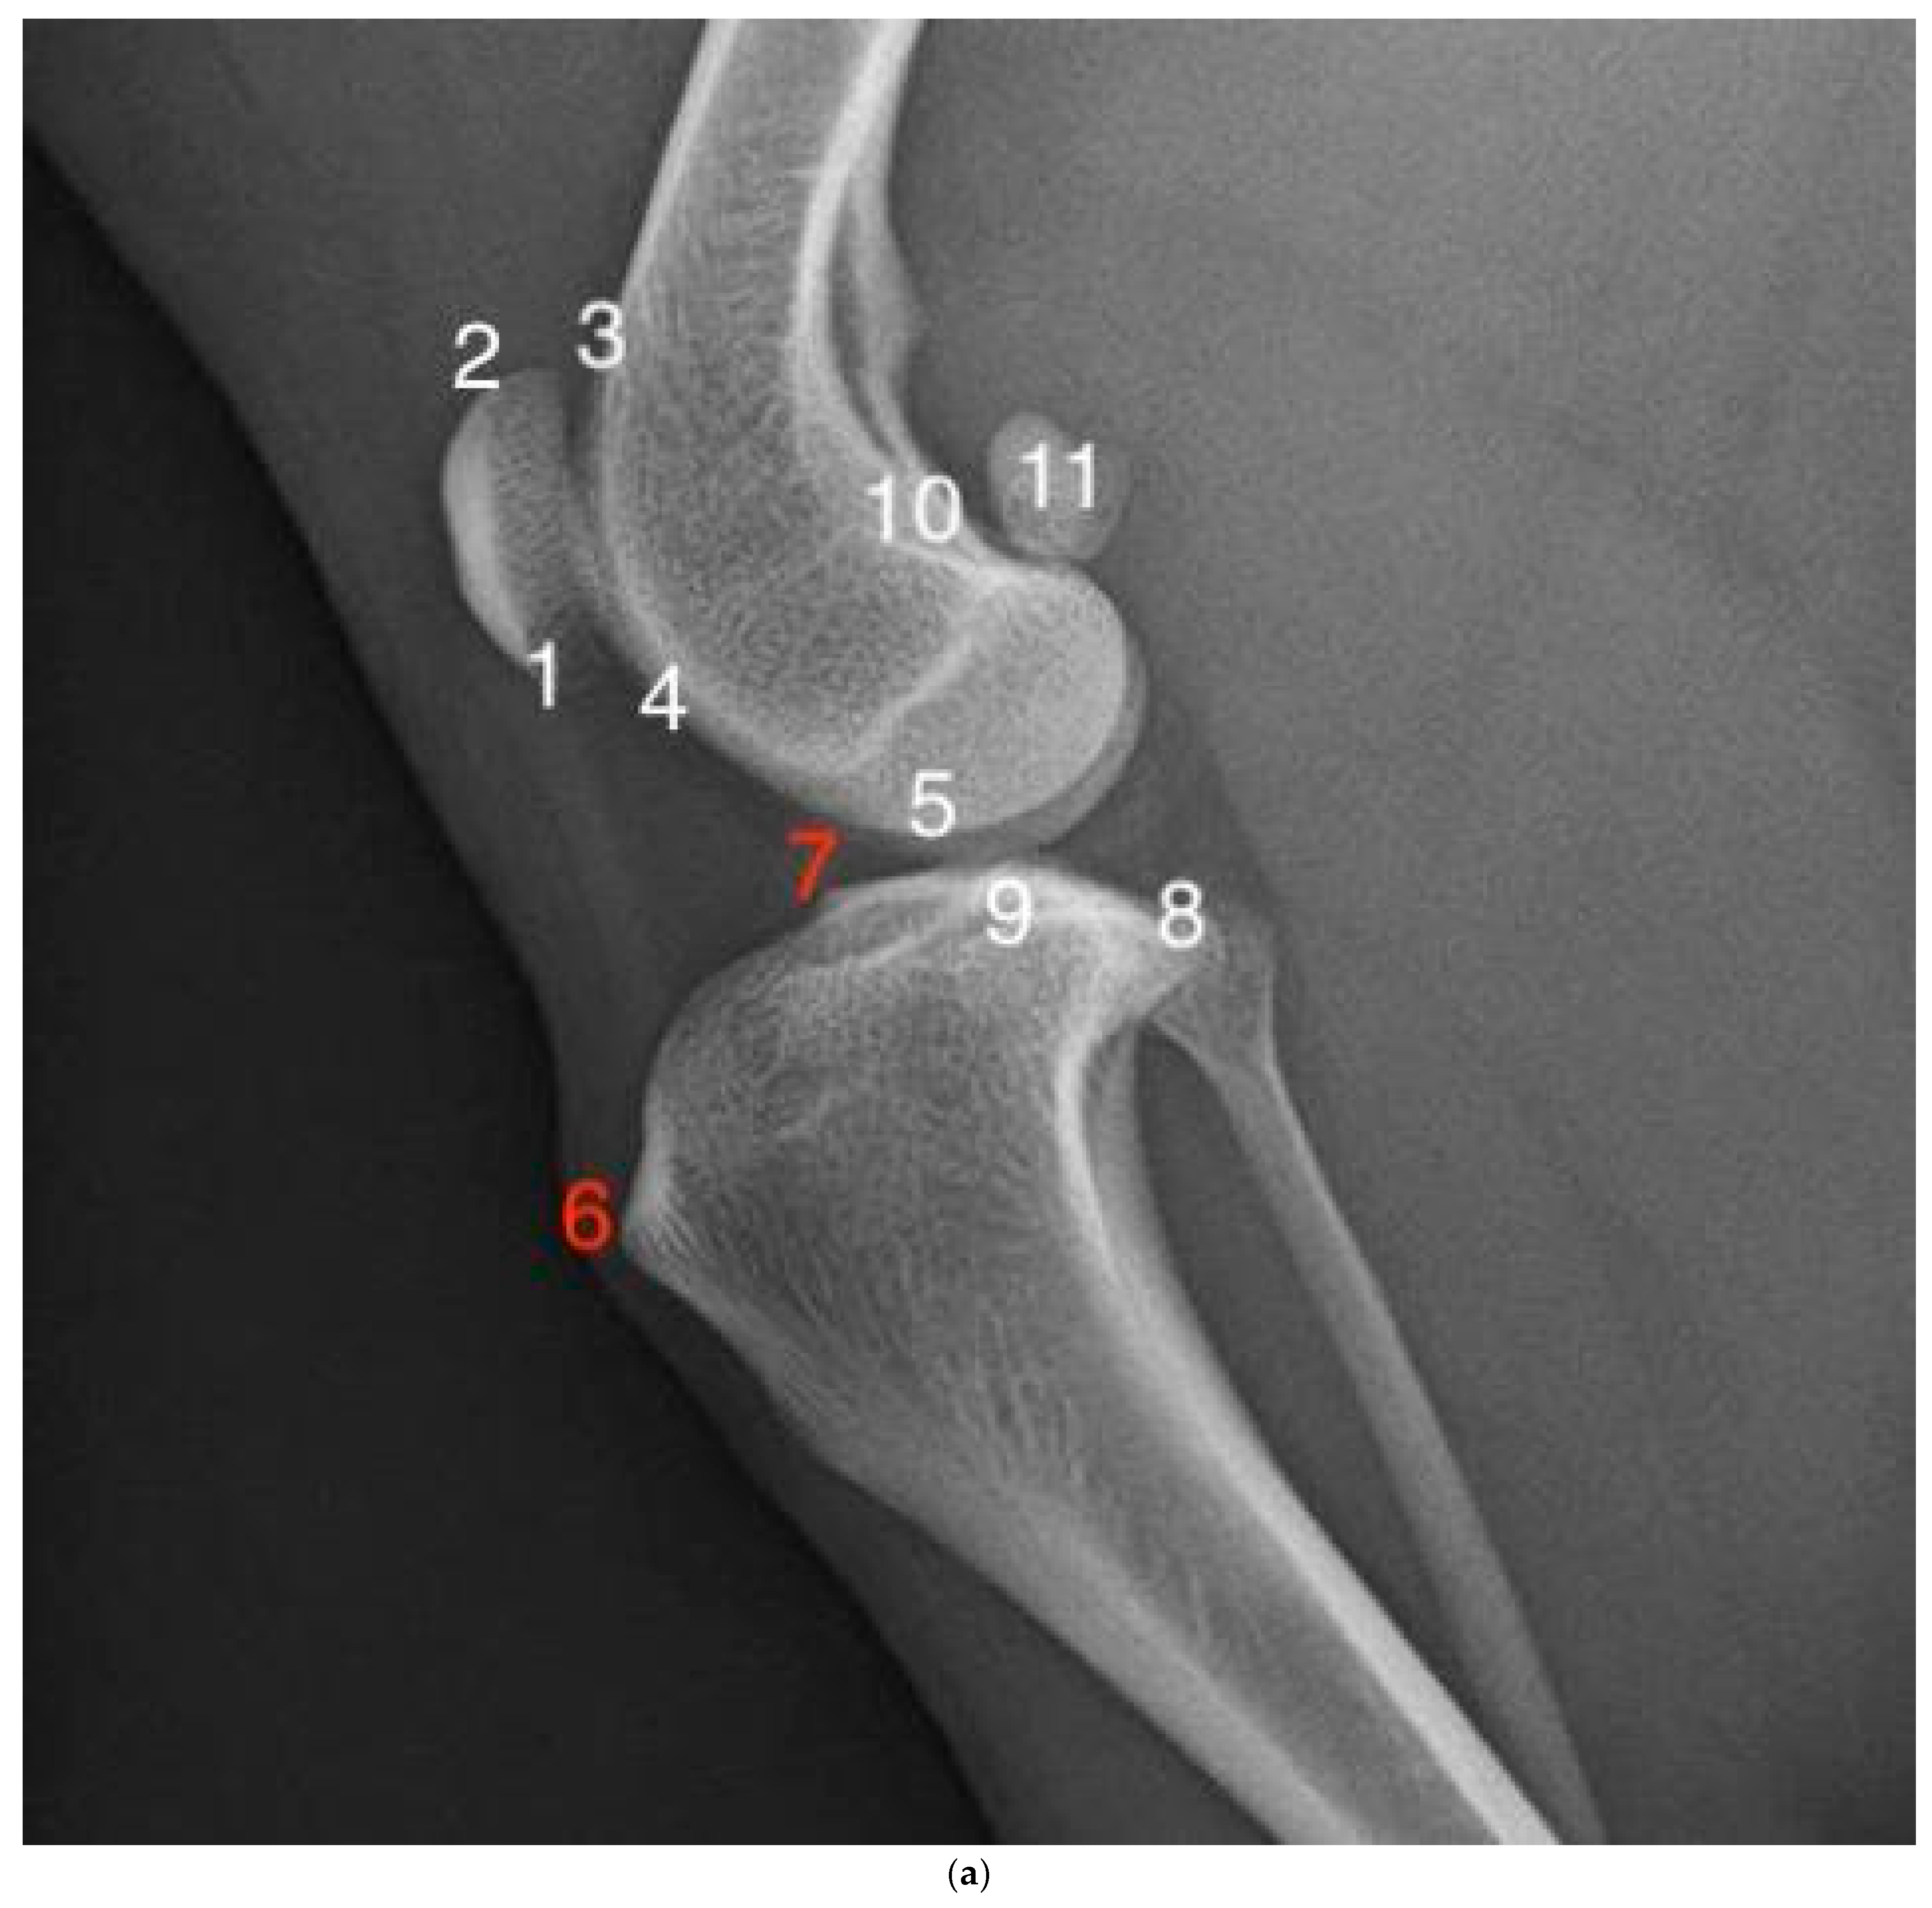

2.3. Radiographic Examination and Scoring

| Grade | Severity | Changes |

|---|---|---|

| 1 | No radiological signs of osteoarthritic changes | No osteophytes/enthesophytes detectable at bone points. The bone contour corresponds to normal anatomy. |

| 2 | Minor radiographic evidence of osteophytic changes | Osteophytes/enthesophytes are detectable but do not result in loss of distinctness of the bone contour. |

| 3 | Moderate radiographic evidence of osteoarthritic changes | Osteophytes/enthesophytes are clearly visible, and loss of bone contour may be present. |

| 4 | High-grade radiographic evidence of osteoarthritic changes | Osteophytes/enthesophytes extend well beyond the bone contour and may be associated with significant loss of distinctness of the bone contour. |